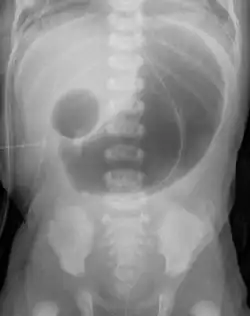

| Radiograph with double bubble sign indicating duodenal atresia | |

If not diagnosed in utero, infants with intestinal atresia are typically diagnosed at day 1 or day 2 after presenting with eating problems, vomiting, and/or failure to have a bowel movement.[3] Diagnosis can be confirmed with an X-ray, and typically followed with an upper gastrointestinal series, lower gastrointestinal series, and ultrasound.[5][3]